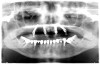

Utilizing two axially orientated implants in the anterior region and two tilted posterior implants (Figure 1), the All-on-4 concept facilitates an avoidance of anatomical structures as well as the accurate placement of longer implants into better-quality bone anteriorly. The tilted posterior implants are key components of this concept. In the mandible, tilted posterior implants facilitate excellent bone anchorage without interfering with the mental foramina. In the resorbed posterior maxilla, the tilted implants are an alternative to sinus floor augmentation.

Fig 1. A radiograph of the All-on-4 concept depicting two axially orientated implants in the anterior and two tilted implants in the posterior.

Figure 1